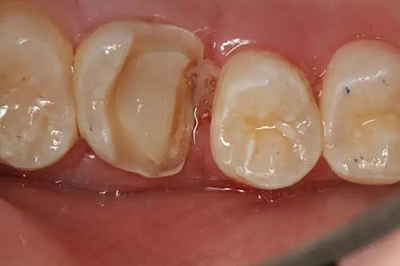

患者男性,35歲,B6銀汞充填后食物嵌塞,要求重新充填,口內(nèi)檢查見B6近中鄰頜面銀汞充填物,局部缺損,有繼發(fā)齲,去除原充填物及繼發(fā)齲,發(fā)現(xiàn)齲壞位于牙齦下方,給予冠延長手術,同期嵌體預備,后一次性取模。(同樣設計為齦上邊緣)

硅橡膠取模后,灌注模型,科爾琥珀樹脂制作嵌體。